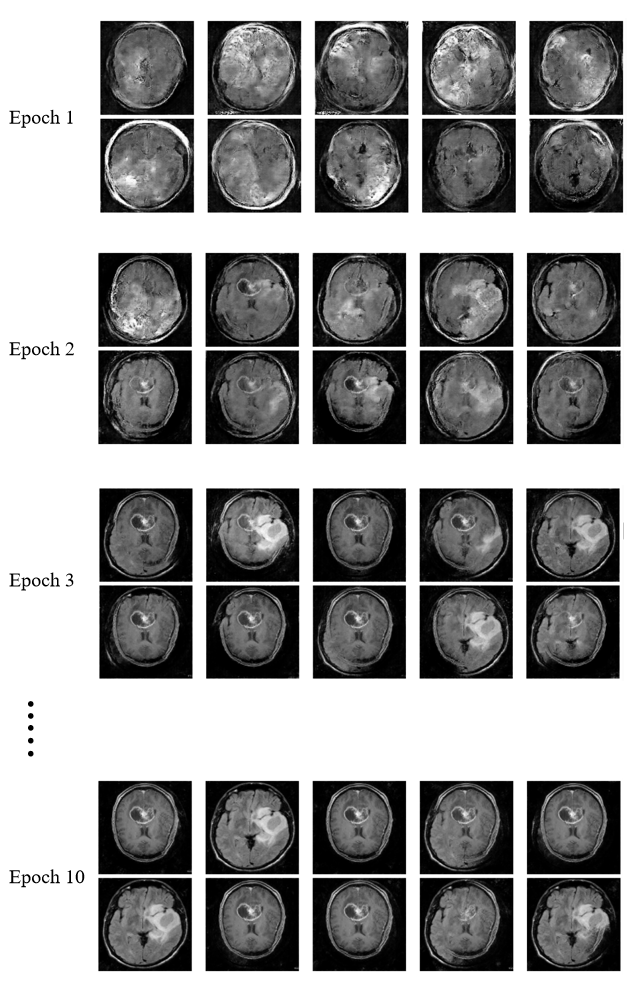

Refer to caption

Figure 3: Progression of Brain Tumor MRI Image Generation Across Training Epochs.

The first few attempts (epochs 1-3) didn’t look great they were blurry, oddly shaped, and only somewhat resembled real MRIs. But as training continued, the improvements were really noticeable. By epochs 5-10, the model started generating scans with clear and sharp anatomical details and realistic looking tumors, complete with the subtle textures see in real patient images which is shown in Fig. 3. These side by side comparisons were eye opening they clearly showed how much the model had improved. It clearly showed that, our model had actually learned to create convincing synthetic brain scans.

IV-B Performance Metrics

In the first few epochs, the generated images were blurry and lacked clear structure, which is shown in Fig. 3. By epochs 2 and 3, the images started to improve its structure. Now the faint outlines of features and small spots also showed, which is possibly brain tumors begin to appear. Although they are still still blurry and not very clear at that moment. In epochs 4 and 5, the images become clearer and more detailed and the quality of the images improves with an increase in the epochs. The generated brain image shapes start to look clearer, and the fake brain tumor images look more real. They fit in with the rest of the images instead of looking like random spots. After 6 epochs, the generated image quality is amazing. The images look like real MRI scans. At this stage, anyone can see the brain parts and identify the tumor. The model learns how real medical images are supposed to look. Finally, by epoch 10, the results look quite good. The MRI brain tumor images look almost like real ones, with clear tumor details and realistic.